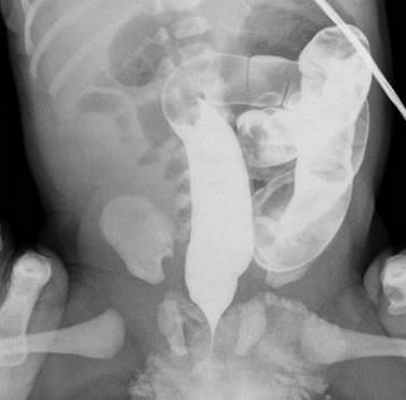

При первом типе мальротации в процессе внутриутробного развития происходит только один поворот средней кишки, в результате чего тонкая и толстая кишка имеет одну брыжейку. При ирригографии характерно левостороннее расположение толстой кишки, при этом слепая кишка расположена спереди или слева от позвоночного столба (рис. 1).

Рис. 1. Ирригограмма в прямой проекции. Отмечается расположение петель кишечника преимущественно в левом фланке брюшной полости